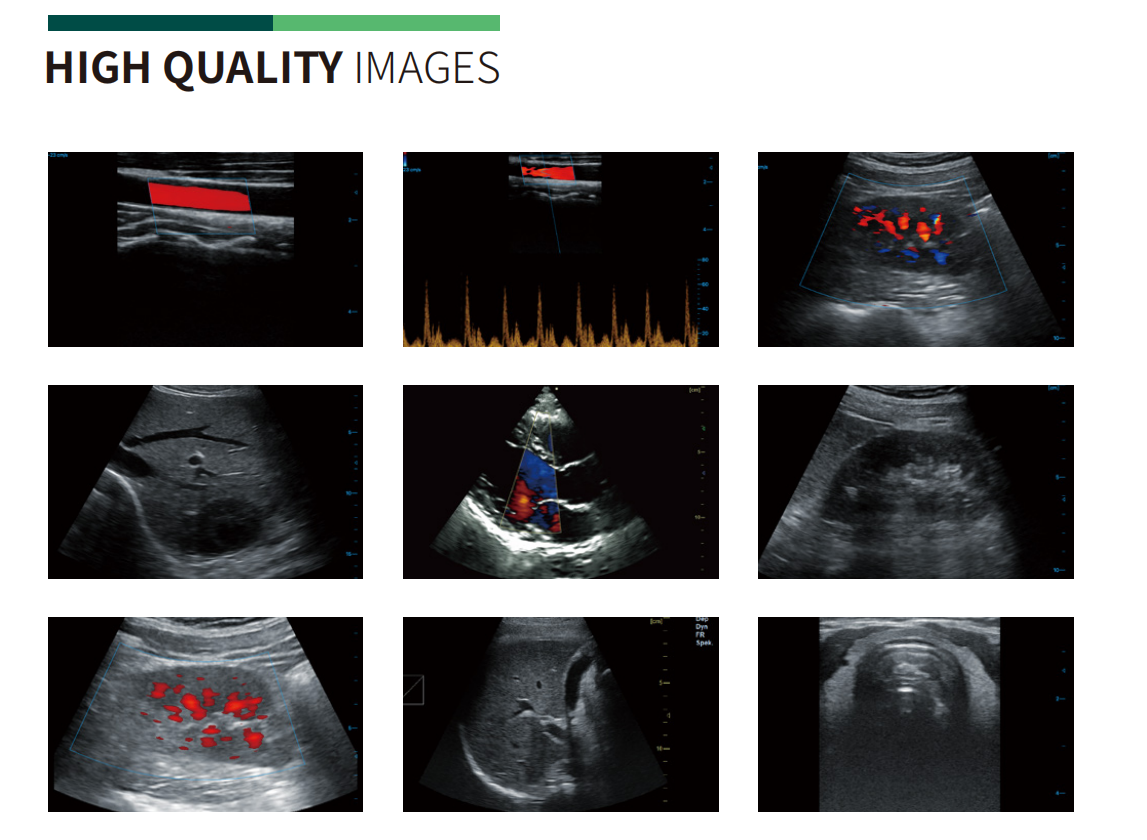

Carotid + CF + PW + Auto Trace

Kidney

Liver + CF

Cardiac + Color M

MSK

Thyroid + CF